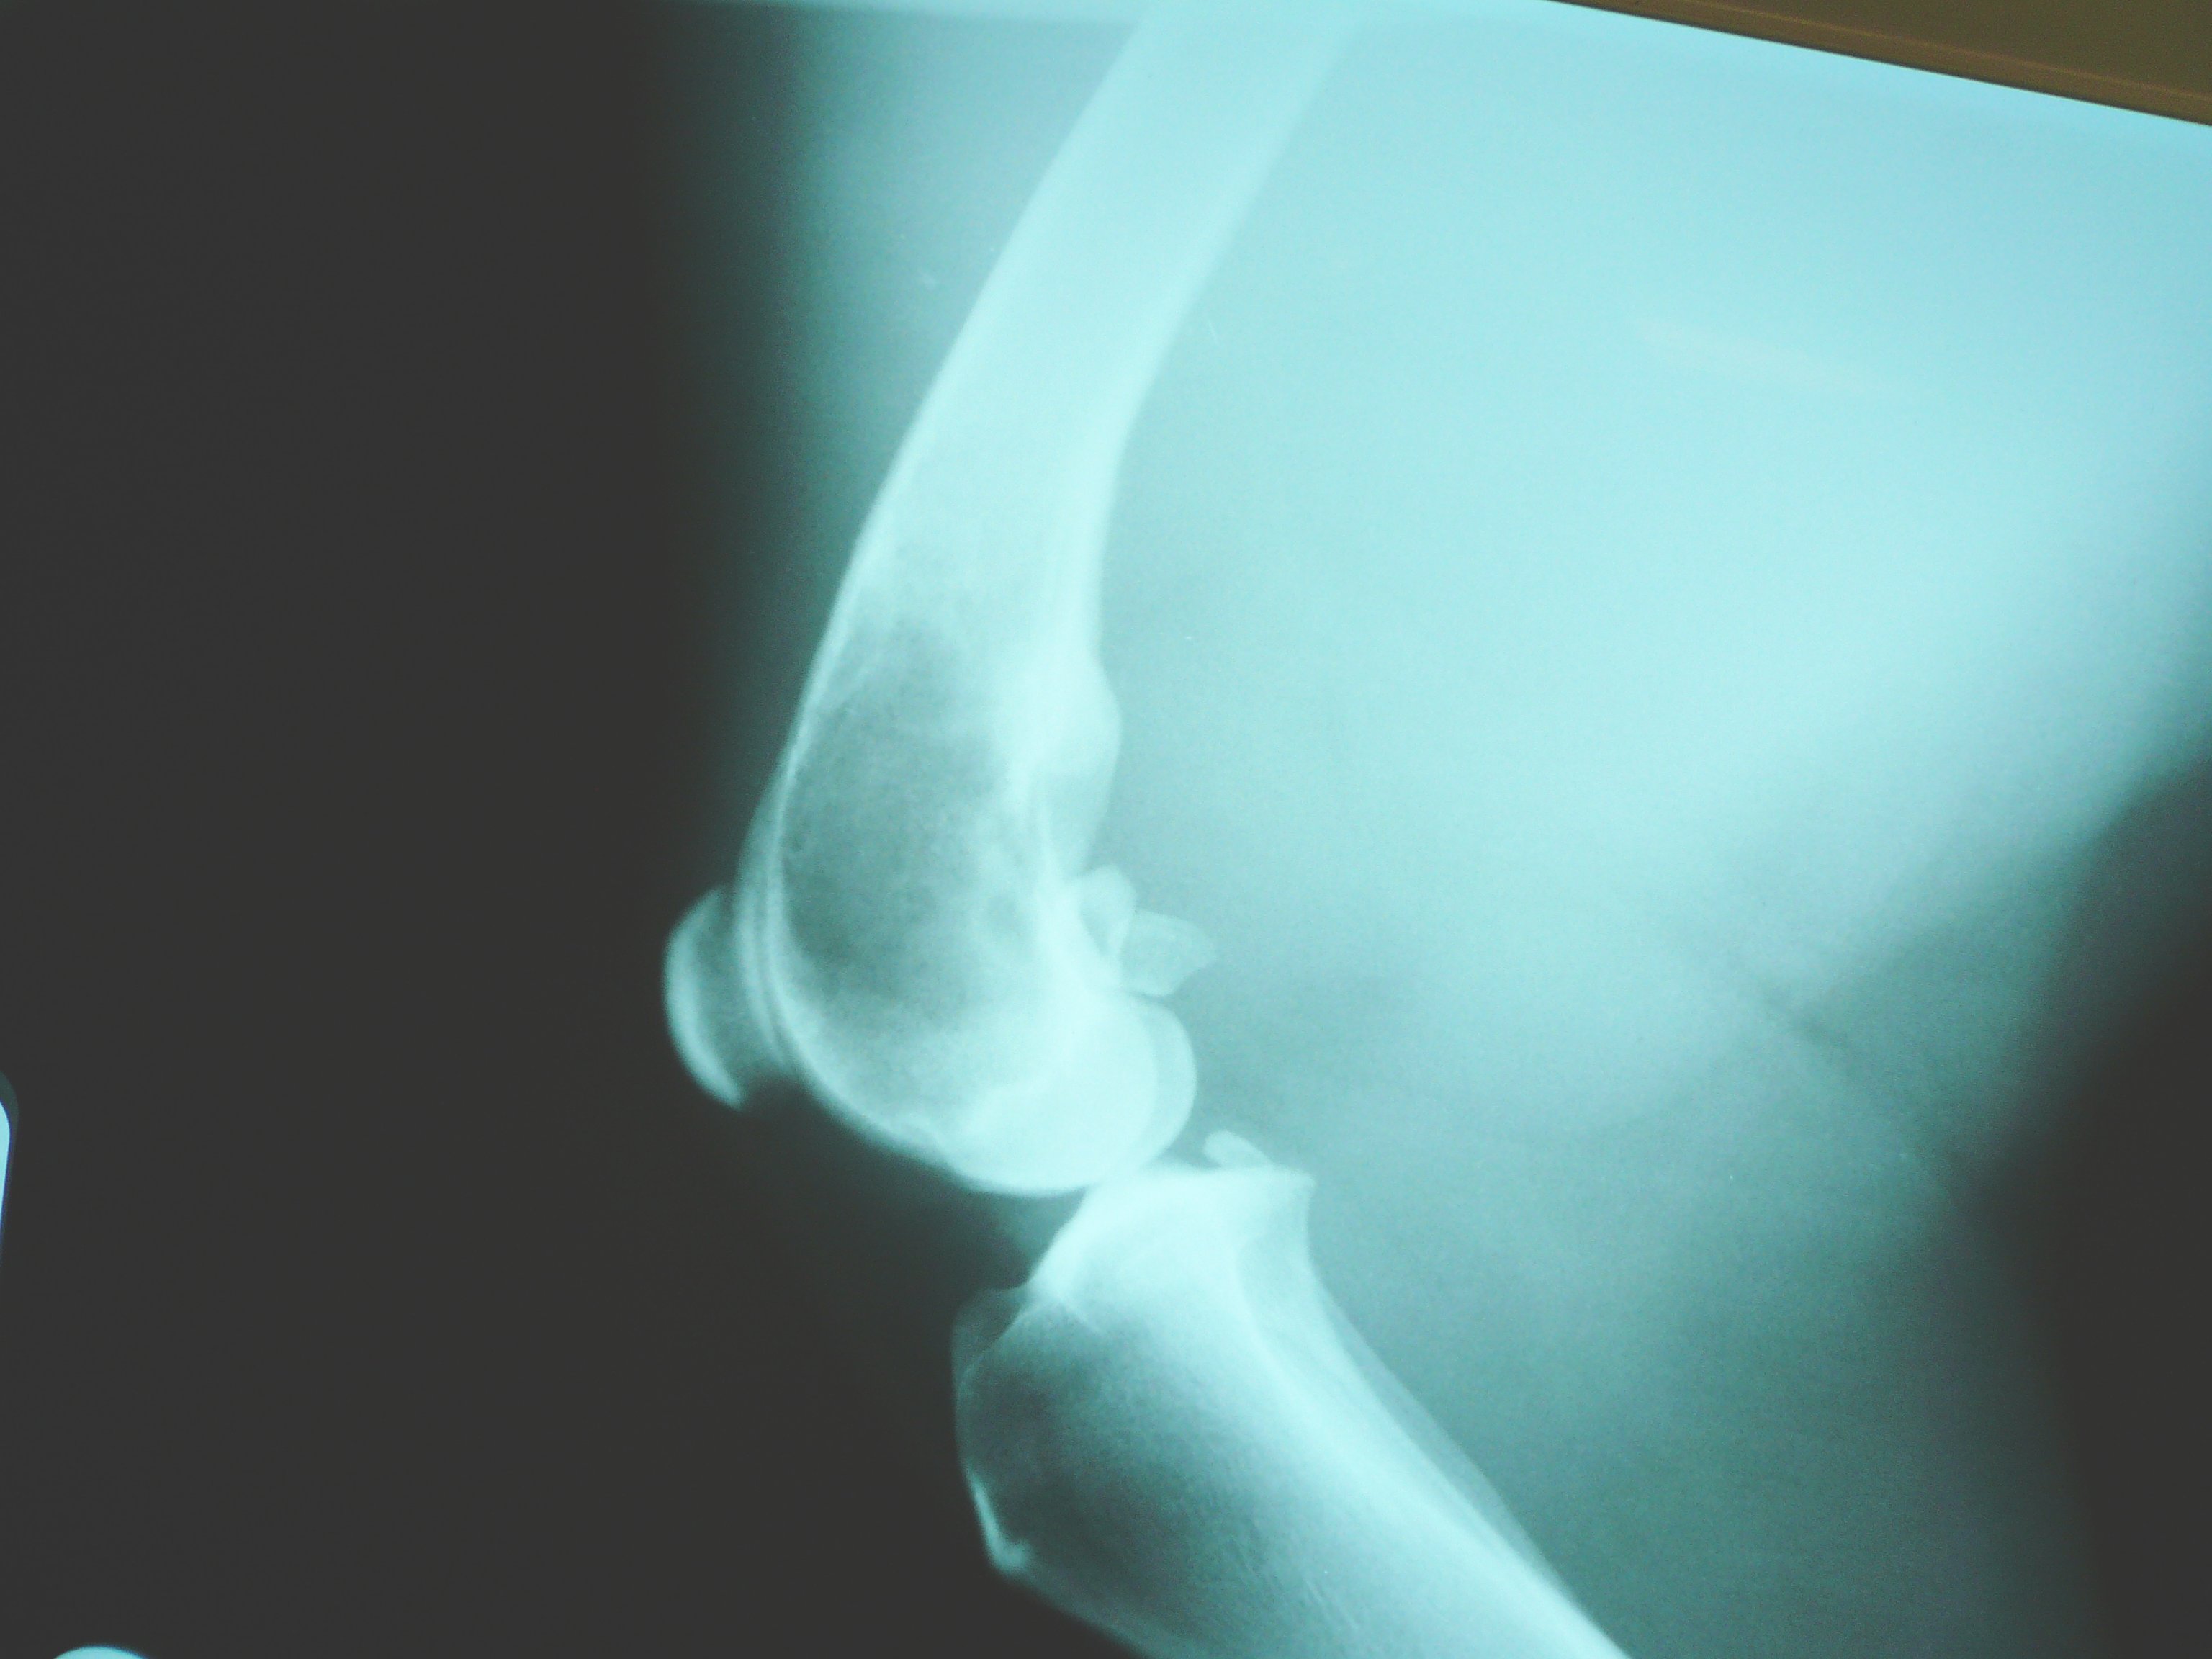

Osteosarcoma occurs spontaneously in humans (usually children) and in dogs with a disease course and severity that are difficult to predict. Some patients respond well to conventional therapies, have a less aggressive form of disease and may survive for decades without recurrence, whereas others respond poorly to treatment or experience recurrence and may survive less than 5 years. This variability has hindered accurate molecular classification of osteosarcomas. Because spontaneous osteosarcoma occurs more frequently in certain breeds of dogs than in others, researchers hypothesized that it would be easier to identify molecular subtypes of osteosarcoma on the more genetically homogeneous canine background. They also believed that these molecular profiles could be used to similarly identify clinically relevant subtypes in human samples in order to better predict therapeutic success.